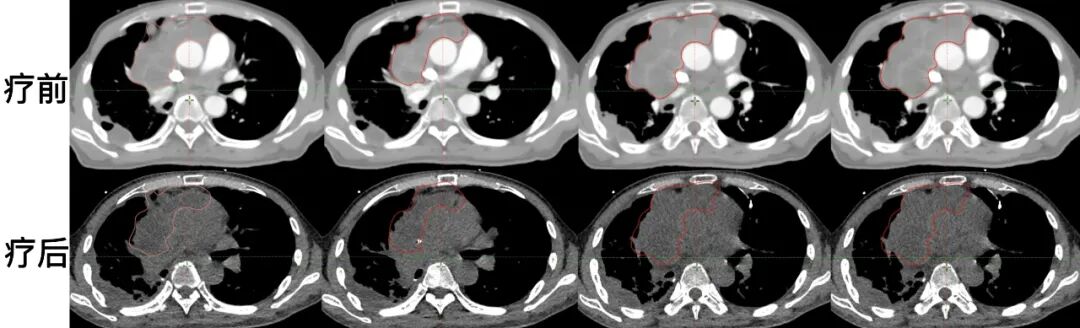

羅先生,55歲,自2010年診斷胸腔內(nèi)惡性孤立性纖維腫瘤,先后接受多次手術(shù)和化療,病情仍反復(fù)進展?;颊叻e極嘗試多種新型治療手段,包括粒子植入術(shù)、動脈灌注術(shù),并接受縱隔腫瘤切除和心包腫瘤切除手術(shù),以及多種化療藥物、靶向藥和免疫藥物治療,然而腫瘤仍持續(xù)進展?;颊呷胱』葜萑悍暖熆茣r,腫瘤病灶增殖快速,基本侵占整個縱膈,并向下侵犯,突破膈肌,侵入腹腔。面對如此巨大的病灶,且纖維肉瘤對放化療敏感性不佳,常規(guī)照射技術(shù)無法控制。放療科團隊決定采用空間分割放療技術(shù)進行治療。

圖注:CT檢查可見,腫瘤范圍巨大,并處于快速增長階段,壓迫心臟及大血管,患者呼吸艱難,需要持續(xù)供氧。

患者剛開始放射治療,便因為腫瘤飛速進展,壓迫大血管,造成上腔靜脈綜合征,出現(xiàn)顏面部嚴(yán)重水腫,氣促,并下腔靜脈壓迫,雙下肢中重度水腫。進一步調(diào)整治療方案,增大單次照射劑量,病情很快得到緩解。一周內(nèi)頭部及下肢水腫消失。放療結(jié)束后,腫瘤病灶發(fā)展得到控制。

圖注:放療前后腫瘤區(qū)域CT對比,上排圖像放療前,腫瘤巨大,壓迫心臟及大血管,廣泛侵犯胸膜,下排圖像治療后,腫瘤病灶有所縮退,發(fā)展得到控制。